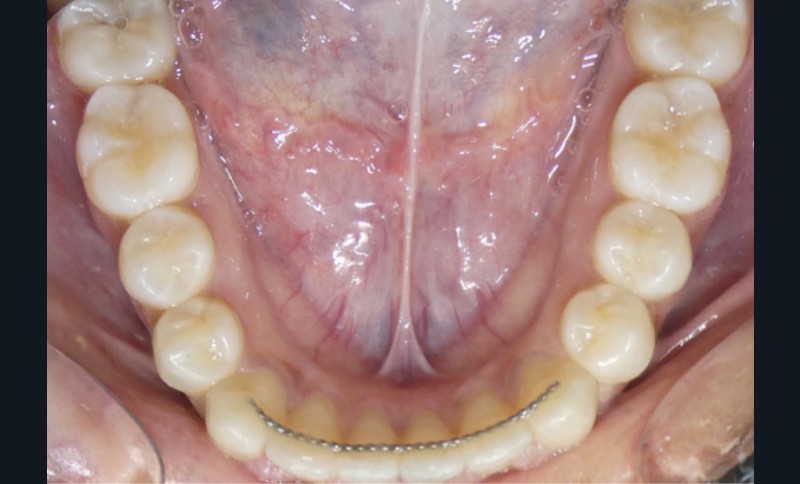

Contention

La contention sera assurée par fil collé maxillaire (après réalisation des restaurations composites) et mandibulaire, ainsi qu’une gouttière thermoformée à port nocturne à l’arcade maxillaire.